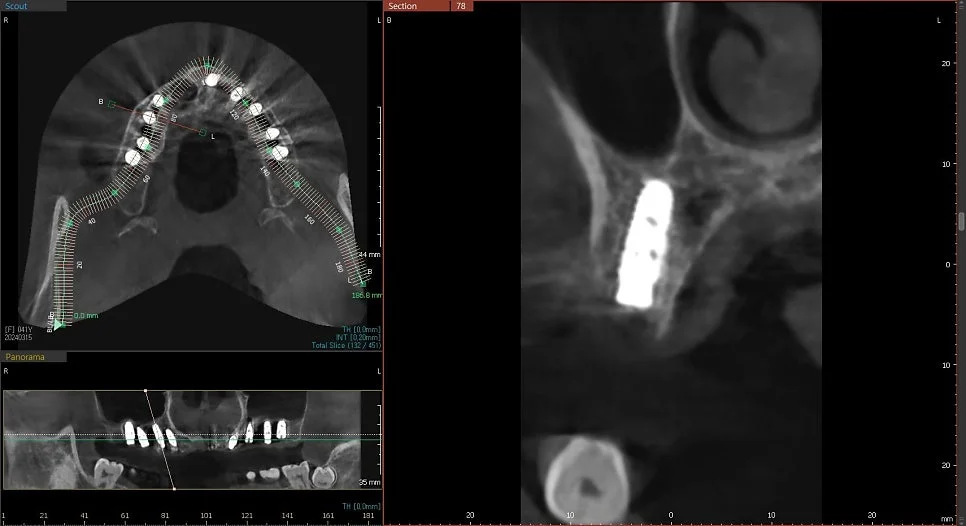

CBCT 단면 – 각 임플란트 개별 검증

CT 상에서 하얀색인 임플란트가 1. 온전히 뼈 안에 잠기게(1~2mm 깊게) 그리고 2. 가급적이면 입천장 쪽으로 식립되었다면 잘 심긴 임플란트입니다. (입술 쪽 뼈는 쉽게 흡수됩니다ㅜ)